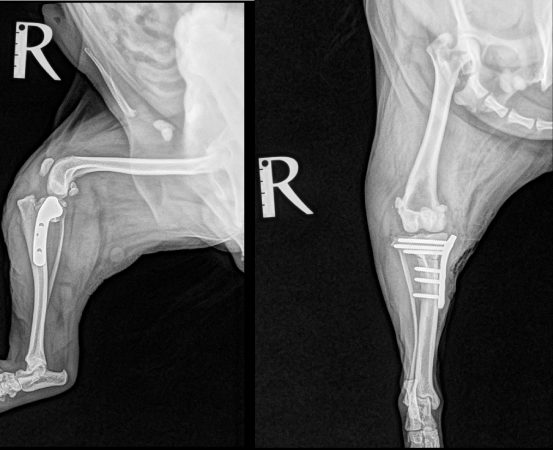

<術後のレントゲン>

骨切りを実施し、脛骨の角度を矯正、プレートで固定することで膝関節を安定させています。